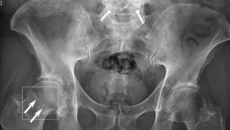

The BoneView software detects potential fractures in X-rays and submits them to radiologists for validation.